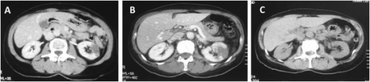

Drug induced vasculitis-a)An ischemic area in left kidney b)increasing of left renal ischemia tissue and novel ischemia right kidney c) after one year reduction of ischemic areas in both kidneys

Renal ischemia also known as nephric ischaemia, is the deficiency of blood in one or both kidneys or nephrons, usually due to functional constriction or actual obstruction of a blood vessel.[1][2]